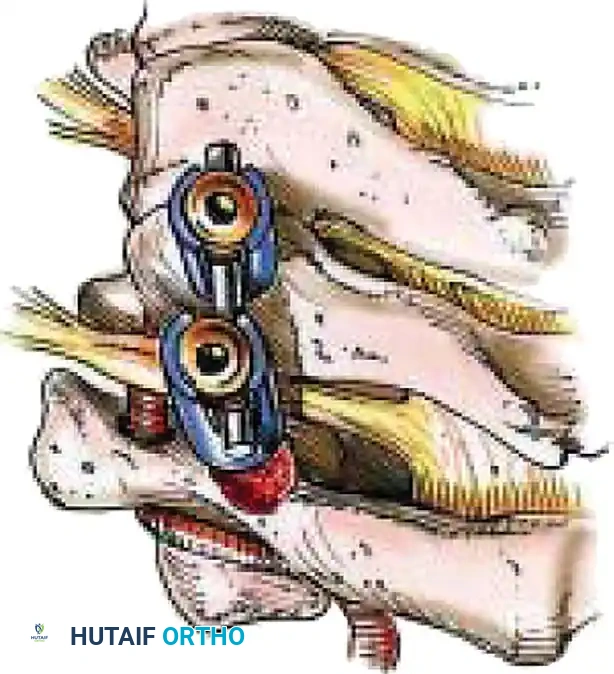

Posterior Cervical Fusion (PCF) and Instrumentation

Indications: Posterior tension band failure, irreducible facet dislocations requiring open reduction, or multi-level instability.

Positioning & Approach:

* The patient is carefully log-rolled prone onto a Jackson table. The head is secured in a Mayfield pin fixator.

* A midline posterior incision is made, utilizing the avascular ligamentum nuchae plane to expose the spinous processes, laminae, and lateral masses out to the medial border of the facet joints.

Surgical Steps:

1. Open Reduction: If a facet is dislocated, carefully lever the inferior articular process of the superior vertebra over the superior articular process of the inferior vertebra using a Penfield elevator.

2. Lateral Mass Screw Fixation:

* Utilize the Magerl or Roy-Camille trajectory.

* Magerl Technique: The entry point is 1 mm medial and 1 mm superior to the center of the lateral mass. The drill is angled 25 degrees laterally (to avoid the vertebral artery) and 15 degrees cephalad (to avoid the exiting nerve root).

3. Rod Contouring: Contour titanium or cobalt-chrome rods to match the patient's natural cervical lordosis and secure them to the screw heads with set screws.

4. Decortication and Fusion: Aggressively decorticate the lateral masses and facet joints with a high-speed burr. Pack the gutters with cancellous autograft (often harvested from the iliac crest) or high-quality allograft.

Fig 7. Posterior cervical lateral mass screw and rod construct, providing excellent biomechanical stability for posterior tension band failures.